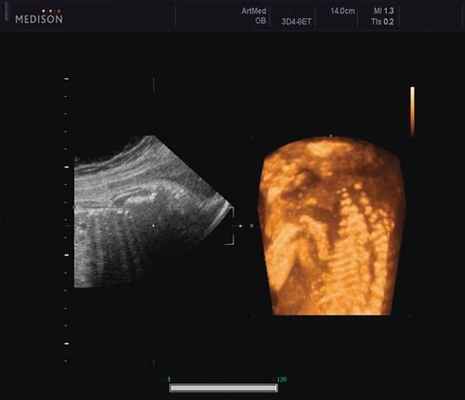

Ребра левой стороны были сближены, межреберные промежутки уменьшены по сравнению с противоположной стороной (рис. 5, 6). Другой патологии у плода не было выявлено. Заподозрен врожденный сколиоз, основой которого является наличие боковых полупозвонков (hemivertebrae) или боковых клиновидных позвонков. В 26 нед ультразвуковая картина сохранялась. При проведении трехмерной эхографии получено отчетливое изображение асимметрии реберных дуг и сколиотическая деформация позвоночника.

Рис. 5. Асимметрия межреберных промежутков в режиме 3D реконструкции.

Рис. 6. Асимметрия межреберных промежутков в режиме 3D реконструкции.